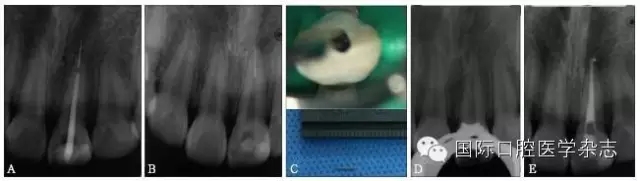

超聲技術(shù)作為經(jīng)典且有效地取出分離器械的方法之一,具有獨(dú)到的優(yōu)勢。超聲工作尖可以在顯微鏡直視下在根管內(nèi)運(yùn)動(dòng),且能夠不對稱地去除分離器械周圍的牙本質(zhì),若只在分離器械一側(cè)局部運(yùn)動(dòng)即能取出分離器械,則有利于保存根管壁較薄一側(cè)的牙本質(zhì),減少牙本質(zhì)的損失。此外,當(dāng)器械分離于根管中下段甚至超出根尖孔,而分離器械較松時(shí),可用超聲工作尖伸入根管內(nèi)分離器械旁邊,利用水流與超聲振動(dòng)將分離器械帶出根管(圖11)。

A:X線片示上頜中切牙根尖部有一分離器械,器械超出根尖孔;B、C:超聲結(jié)合水流沖洗,有時(shí)可意外取出分離器械;D:X線片示分離器械被取出;E:根管預(yù)備并充填至根尖。

圖 11 當(dāng)器械分離于根管中下段甚至超出根尖孔,而分離器械較松時(shí),超聲器械有獨(dú)特的優(yōu)勢